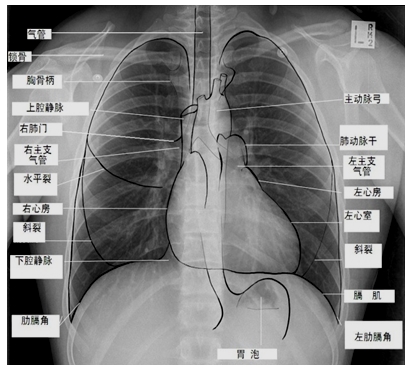

一、正常胸片